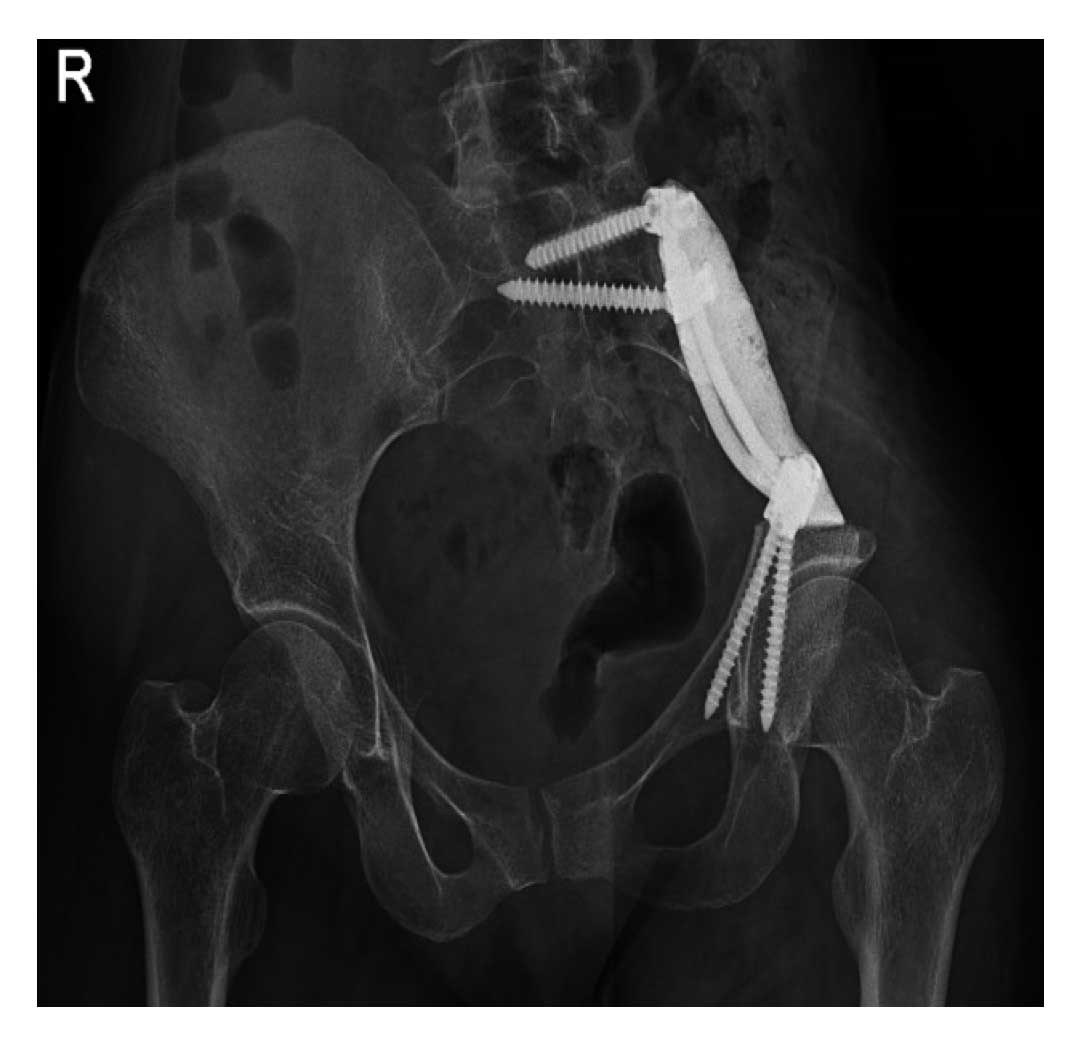

22 yaşındaki kadın hastada yurt dışında tanı konulan Ewing sarkom nedeniyle altı kür kemoterapi uygulanmıştır. Taramalarında metastaz saptanmayan hastaya iliak kanat rezeksiyonu sonrası vida, rod ve kemik çimentosu ile rekonstrüksiyon işlemi yapılmıştır.

Sonrasında vida, rod ve kemik çimentosu ile rekonstrüksiyon uygulandı.

Ameliyat Sonrası: İliak kanat çıkarıldıktan sonra rod/vida ve kemik çimentosu ile yeniden yapılandırma görülmekte.